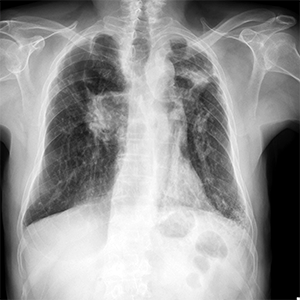

Noviembre 2025. Hospital Italiano

Masculino de 61 años. Masa dolorosa en cara anterior de pie derecho.